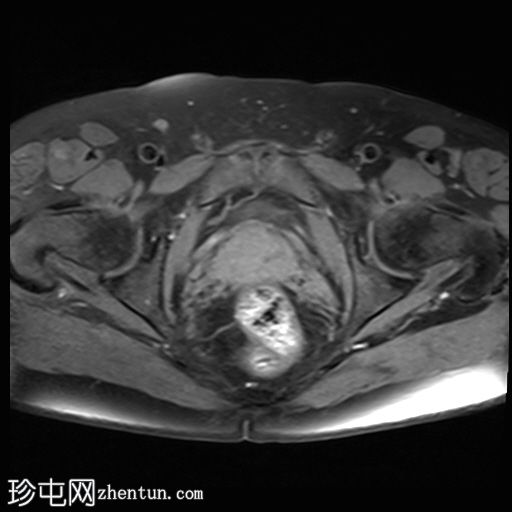

冠状位

T2

位于5点钟和6点钟位置之间,在STIR和T2加权图像上呈高信号。

瘘管起源于括约肌间平面附近,穿过肛门内外括约肌,并延伸至左侧坐骨肛门窝。瘘管内充满液体信号,周围有轻微水肿。肛提肌上方未观察到颅骨延伸。

根据圣詹姆斯大学医院的磁共振分类系统,该病例被归类为III级左侧肛周经括约肌瘘,左侧坐骨肛门窝可见炎症改变。